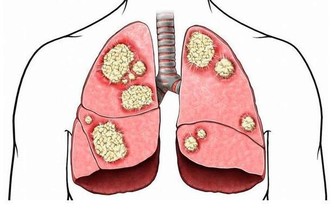

外耳道受刺激,引起病毒感染,發生外耳道乳頭狀瘤。雖說一般情況下,這種腫瘤都屬於良性,但是其實也有2%的惡變率。